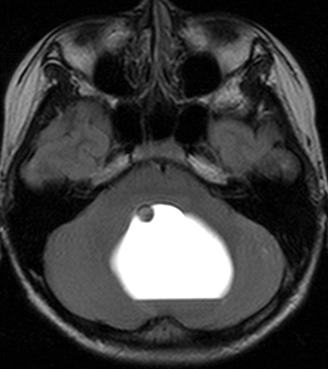

20代女性に偶然発見された視床下部(第3脳室)腫瘍です,T1低信号,T2で高信号,右側のガドリニウム造影では全く増強されません。毛様細胞性星細胞腫と診断できます。眼科での視野検査で視野欠損はありませんでした。生検術もなにもせず経過をみました。

左が初診時,右が5年後のMRI画像です。腫瘍の大きさは全く同じです。このような腫瘍はしばしば経験します。慌てて生検術や開頭手術など計画しないで,画像診断をしっかりすることが大切です。